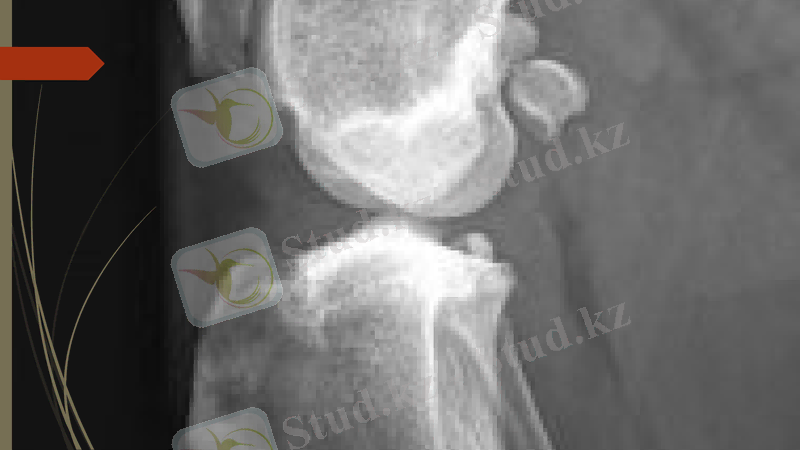

Рентген сәулесімен зерттеу әдісі - сүйек пен каңқаны зерттеп, диагноз қоюдағы ең жоғары сапалы эдіс болып табылады. Бүл әдістің тек сүйектін қүрылысын ғана емес, сондай-ақ сүйектену, сүйектің өсу динамикасын, тірек-қимыл системасының қимылдау кезеңіндегі ауруларын, сүйекті коршал түрған үлпалардың да ауруларын зерттеуде маңызы зор.

Рентгенограмманы өзара перпендикулярлы екі проекцияда - т і к және ж а н ы н а н (немесе қ а п т а л), ал жануарлардың кейбір мүшелерін (бас қаңқасын, иық, асық буындарын) қиғаш проекцияда түсіру қажет

ІрІ малдардын сирағын рентгенограммаға түсіру әдістемесі